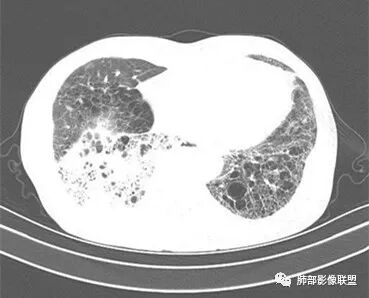

2.影像表现:肺气肿背景,右肺下叶呈现明显网格影及蜂窝影、枯枝征,边缘膨隆、叶间裂向前方推移。病灶密度不均,前份见不规则片状实性密度区,实性部分轻度强化,边界不清,周边特征掩盖不清。支气管主要分支显示,呈枯枝征。纵隔窗病灶密度偏低,病灶内血管影边缘稍显模糊,未见明显液化坏死区。

余双肺未见明显结节影。

右侧肺门淋巴结肿大,中央低密度;纵隔见轻度增大淋巴结。

3.综合分析:临床方面:慢性病程、急性发作,呼吸道症状伴发热,炎性指标升高,提示存在感染可能;CA199升高,但相对特异性不高。影像双肺气肿,右肺下叶蜂窝状改变明显,夹杂实变密度区,支气管相关但未见阻塞,较常见于感染性病变,如G-杆菌感染等。蜂窝影什么时候出现我们不得而知,实变区周边特征掩盖不清。

前后三月余病灶变化不明显,右肺门异常肿大淋巴结让人警惕恶性病变可能性。

因为有肺气肿背景、有蜂窝,周边特征及张力等都不能作为判断依据或参考。单肺叶蜂窝影伴实性密度区被确诊为肺腺癌的例子已不少见,敬请留意。